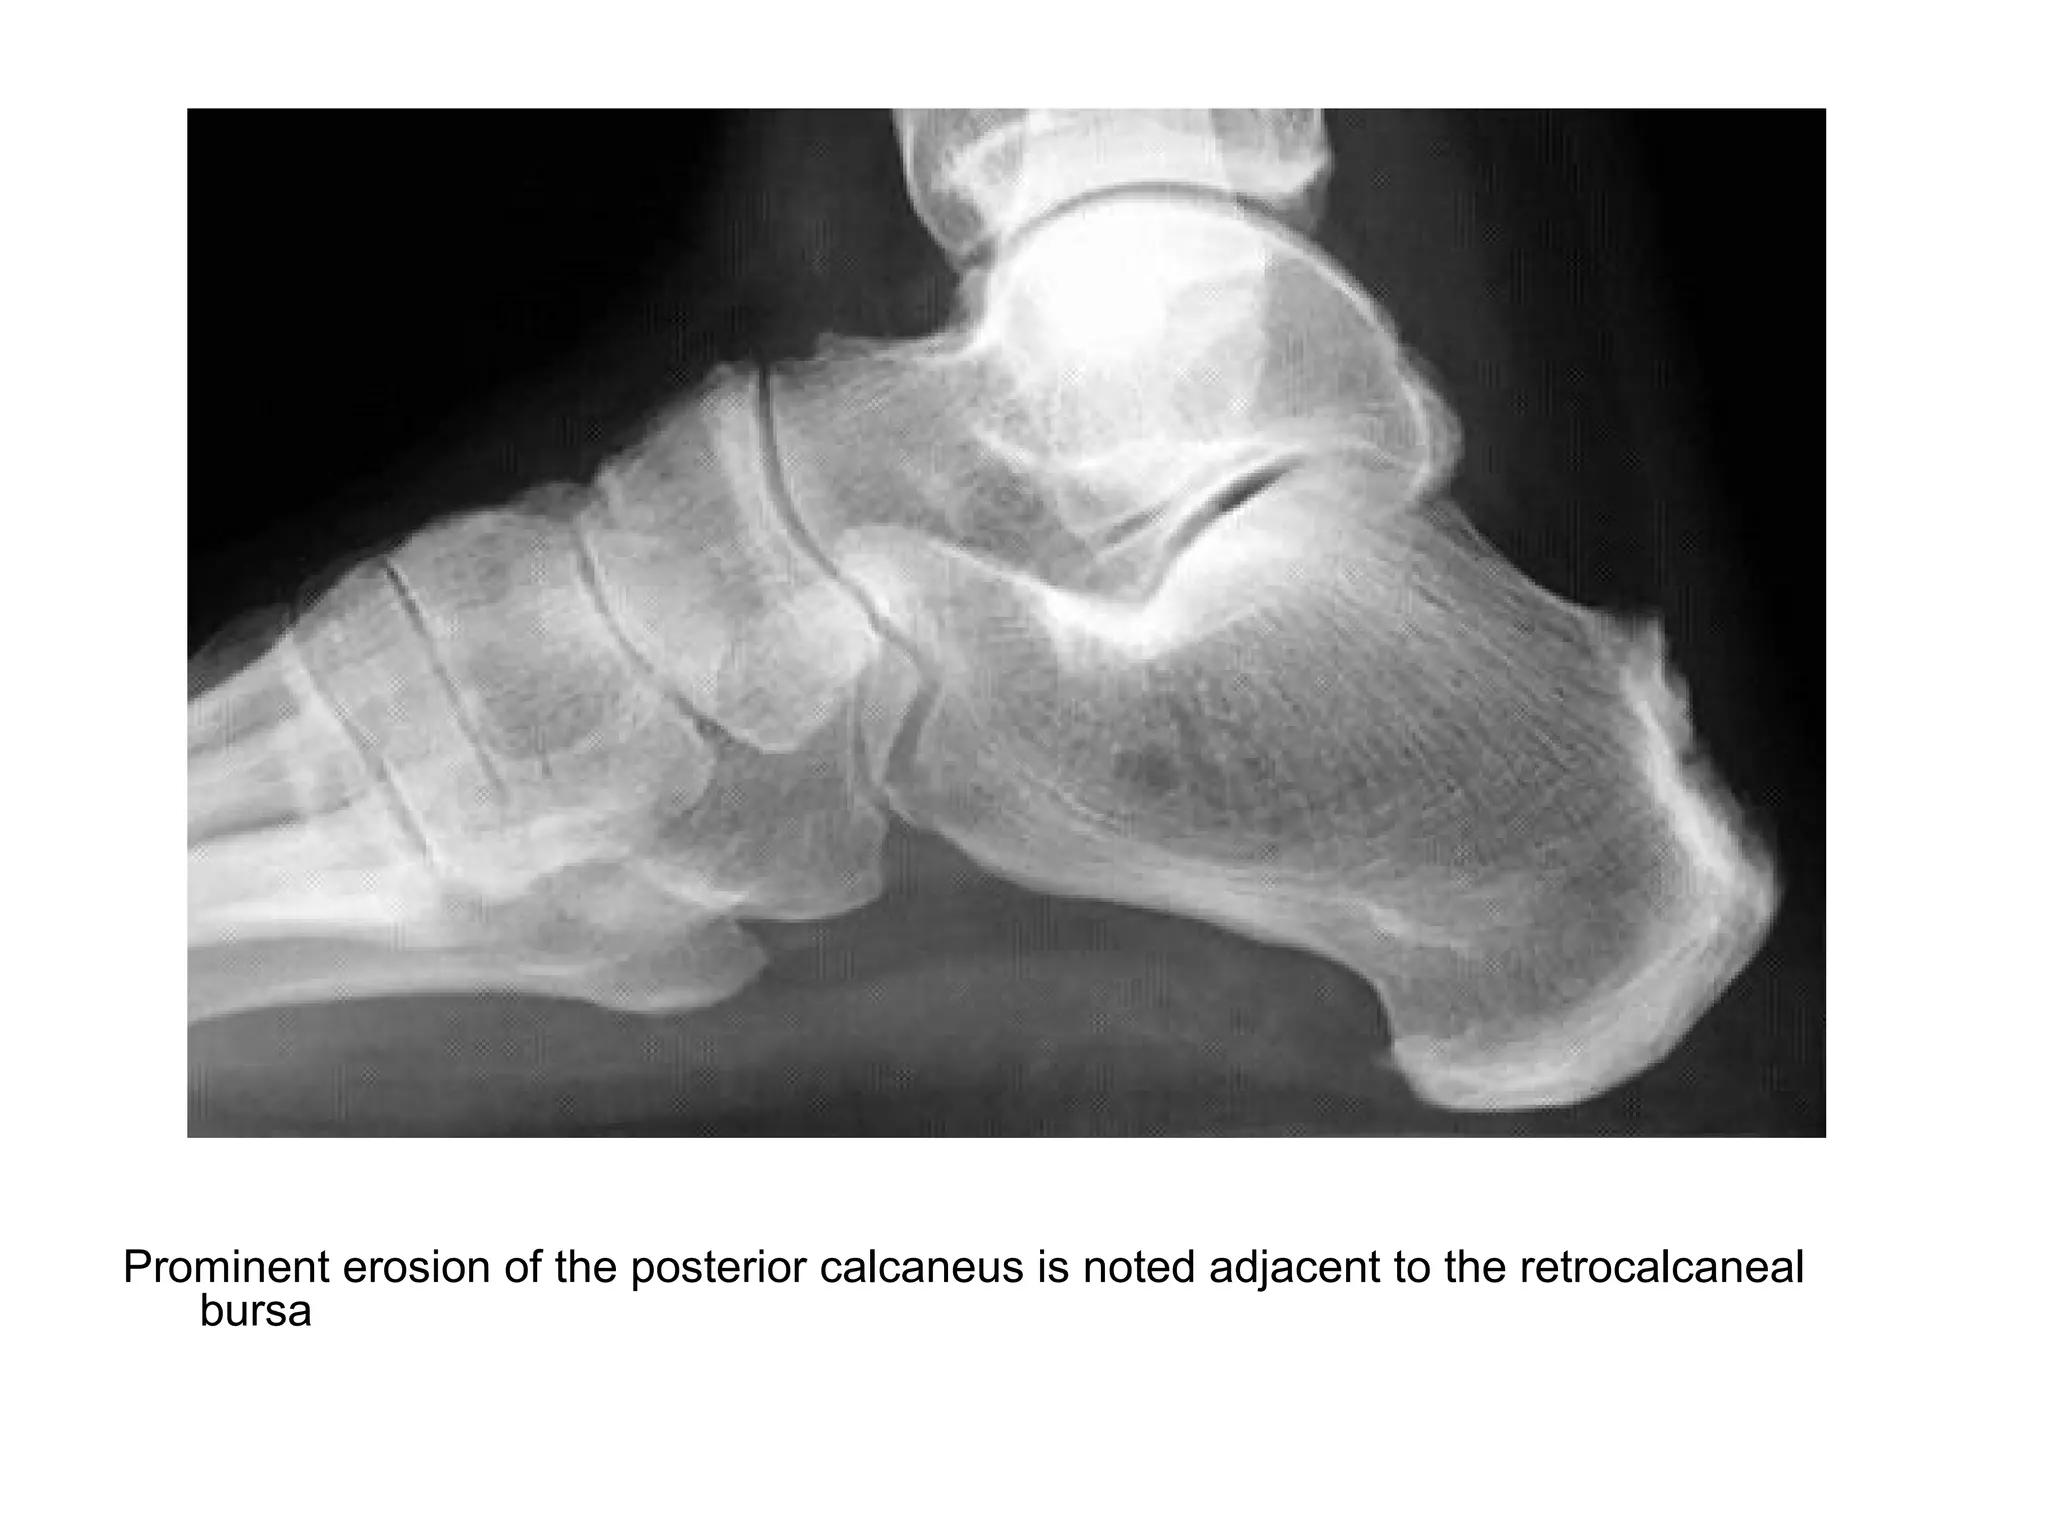

Prominent erosion of the posterior calcaneus is noted adjacent to the retrocalcaneal

bursa